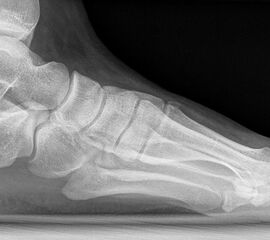

Standard ist die belastete Röntgenaufnahme des Fußes dorso-plantar und seitlich. Günstig ist eine Röhrenkippung von 10°-20°, um die Gelenke der Lisfranc-Linie einsehen zu können.

• Hallux valgus Winkel

• Hallux valgus interphalangeus Winkel

• Intermetatarsalwinkel I zu II

• Distaler Metatarsale Gelenkwinkel (PASA)

• Form des Mittelfußknochenkopfes

• Winkel Metatarsale I Basis zum Os cuneiforme mediale

• Metatarsalindex

• Elevation/ Plantarisierung I. Strahl

• Pes metatarsus adductus

• Wachstumsfugen

• Coalitiones

• Akzessorische Knochen